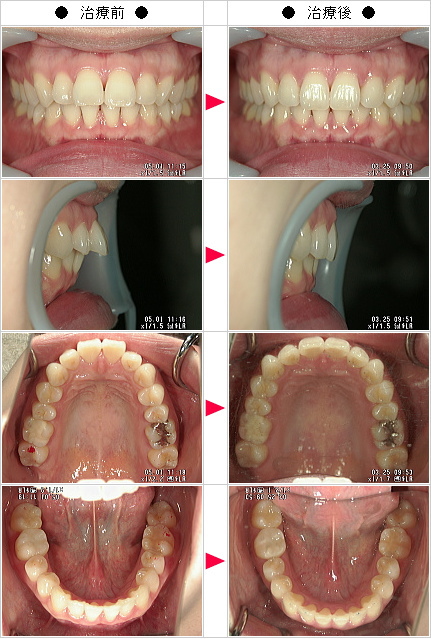

☆出っ歯矯正の治療症例[美絵様 32歳 女性]